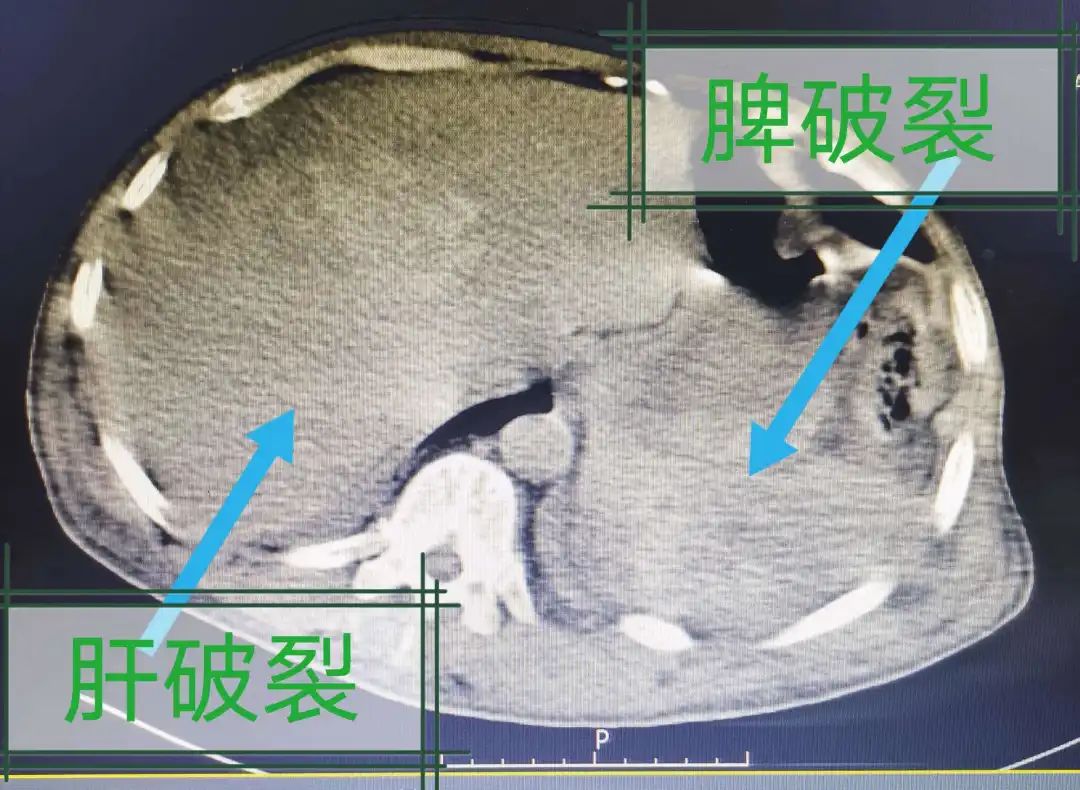

高血压、高血脂、冠心病等问题严重的甚至出现脾破裂,危及生命

避免脾大、脾水肿、脾破裂